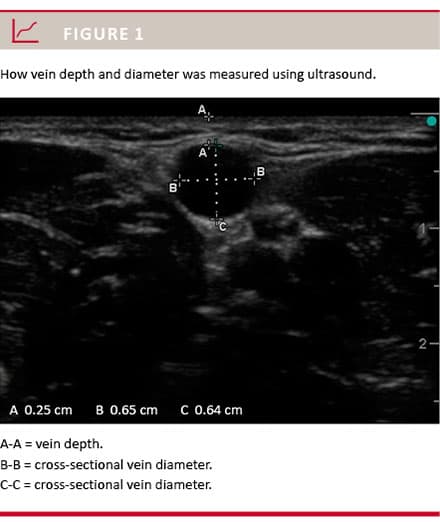

Veins were identified as: superficial veins (depth ≤ 10 mm) or deeper veins (depth > 10 mm). Vein depth was measured as the shortest distance from the skin to the inner venous wall (Figure 1). If more superficial veins were identified, the most superficial vein with a cross-sectional diameter of more than 2.5 mm was chosen.

If only smaller veins were present, the most superficial vein was chosen. When deeper veins were identified, the vein with the largest cross-sectional diameter was measured (Figure 1). If both superficial and deeper veins were identified, a cross-sectional diameter > 2.5 mm had a higher priority than vein depth. The US probe was oriented to obtain a cross-sectional view of the vein and to optimise the image with respect to gain and depth. The smallest possible pressure was applied to the skin when optimising US images. When the optimal image was obtained, we used the freeze function and measured cross-sectional diameter and depth using the caliper function (Figure 1). Doppler flow in the vein was also recorded to verify venous flow. If venous stasis had been applied, Doppler flow was recorded immediately after the venous stasis was released.